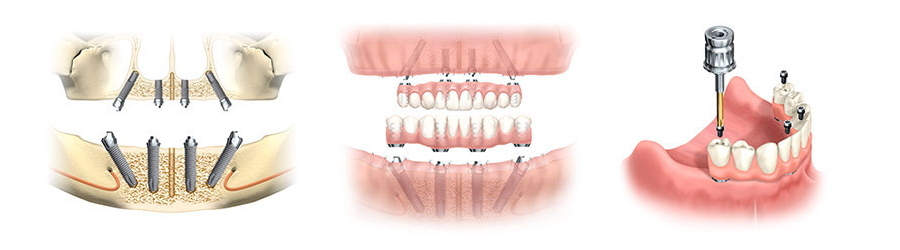

オールオンフォー(All-on-4)オールオンシックス(All-on-6)では、骨のある部分へ最少4本のインプラントオペで全ての人工の歯を支えることができます。

オールオンインプラント治療は、CTデータをもとにコンピューターによるシミュレーションプログラムで設計し患者様専用に作成した手術用ガイドを用いる事で安全に治療を行うことができます。

オールオンインプラントオペをするためにCTデータをもとにオペの設計をし、インプラントをいれる位置や直径、長さを決め患者様専用のガイドを作成します。